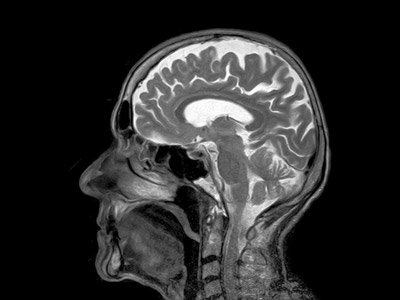

Το τεστ μετρά τα επίπεδα μιας «φωσφορυλιωμένης» μορφής της πρωτεΐνης ταυ, η οποία σχηματίζει παθολογικά συσσωματώματα στον εγκέφαλο των ασθενών με Αλτσχάιμερ.

Στις περιπτώσεις αυτές, απαντήσεις μπορούν να δοθούν μόνο με εξειδικευμένες και ακριβείς εξετάσεις όπως αναλύσεις του εγκεφαλονωτιαίου υγρού και τομογραφία εκπομπής ποζιτρονίων.